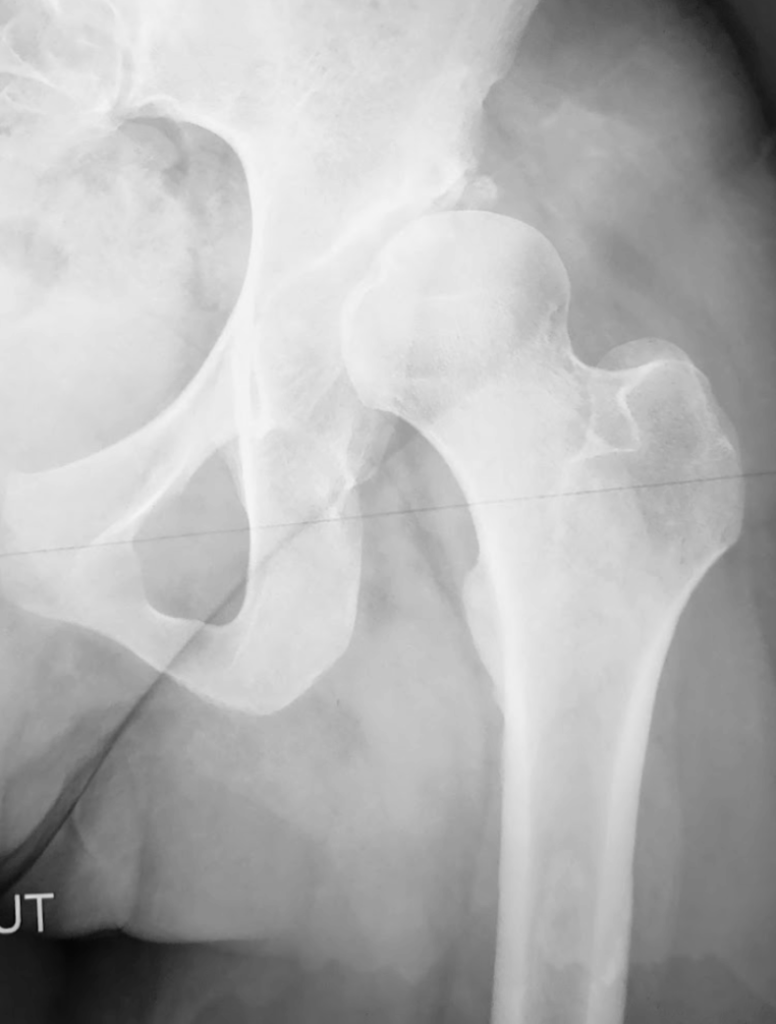

Lorsqu’un patient présente une dysplasie de la hanche, principalement cotyloïdienne (cf chapitre luxation congénitale de la hanche), la tête fémorale se décentre de son axe et l’articulation souffre. L’ostéotomie péri-acétabulaire est une intervention chirurgicale initialement décrite par R. Ganz en 1988, et qui a été modifiée pour être mini invasive à ce jour. Elle est conçue pour corriger les malformations de la hanche telles que l’insuffisance de couverture cotyloïdienne (dysplasie). Elle consiste à recentrer la tête fémorale en réaxant la cavité cotyloïdienne (au niveau du bassin).

Le diagnostic de dysplasie de hanche nécessite une évaluation précise de la morphologie de l’articulation de la hanche et du statut cartilagineux. Pour cela, le chirurgien, après un examen clinique indispensable, fera réaliser des radiographies complètes et un scanner du bassin, pour avoir des mesures précises sur la dysplasie. Il y est souvent associé un examen EOS permettant d’avoir des mesures de longueurs et d’axes au niveau des membres inférieurs.